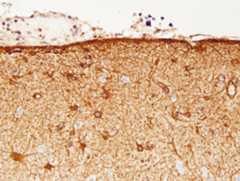

Theinterstitial space of the brain is separated fromthe ventricular CSF by the ependymal lining and fromthe subarachnoid CSF by theglia limitans.The glia limitans is a thick layer of interdigitatingastrocytic processes with an overlying basementmembrane. This layer seals the surface of the CNSand dips into brain tissue along the perivascularspace (see below). External to it is the pia matter,a thin layer of connective tissue cells with a smallamount of collagen. The ependymal barrier is farmore permeable than the BBB.

The major cerebral arteries and veins traverse the subarachnoid space and penetrate into the brain, where they branch into smaller vessels and eventually capillaries. Capillaries are in contact with astrocytic processes. Vessels larger than capillaries are separated from the surrounding brain tissue by a space (theperivascular or Virchow-Robin space), which is an extension of the subarachnoid space. The perivascular space is a component of the“glymphatic”-glial lymphatic- system (analogous to the lymphatic system of the body) which facilitates exchange of molecules between the CSF and the ISF of the brain. CSF flows into brain tissue at the periarterial space, mixes with ISF in brain tissue and effluxes from brain tissue into the CSF along perivenous spaces. It is thought that cardiac pulsations facilitate the exchange of substances between the ISF and the CSF. The glymphatic system helps rid the brain of waste products and maintains homeostasis. Such products include beta-amyloid and tau protein. Thus, the glymphatic system may be important in the pathogenesis of Alzheimer’s disease and chronic traumatic encephalopathy.